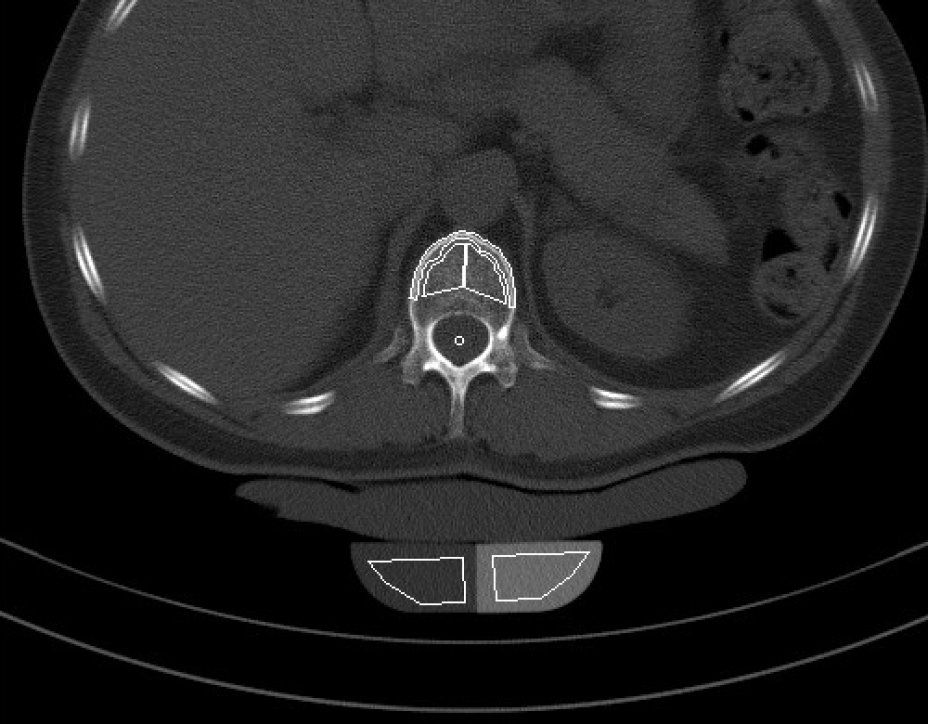

Die Knochendichtemessung mittels Computertomographie (Q.CT) ist eine der genausten Methoden zur Bestimmung der Knochendichte und gilt als Goldstandard. Sie ist sowohl für die Diagnosestellung als auch zur Verlaufskontrolle geeignet. Zur Bestimmung der BMD (engl.: Bone Mineral Density) werden bei der quantitativen Computertomographie ca. 3 bis 4 Scans von der Lendenwirbelsäule angefertigt. Aus der Knochendichte dieser Wirbelkörper wird der Mittelwert ermittelt. Dieser wird dann mit der Knochendichte eines gleichaltrigen Knochengesunden verglichen und in Relation dazu gesetzt. Je nach der Dichte des Knochens wird die Osteoporose dann in mehrere Stadien eingeteilt. Da die Knochendichtemessung (Q.CT) keine Kassenleistung ist, bieten wir die Untersuchung als

IGEL - Leistung an.

Q-CT gestützte Knochendichtemessung